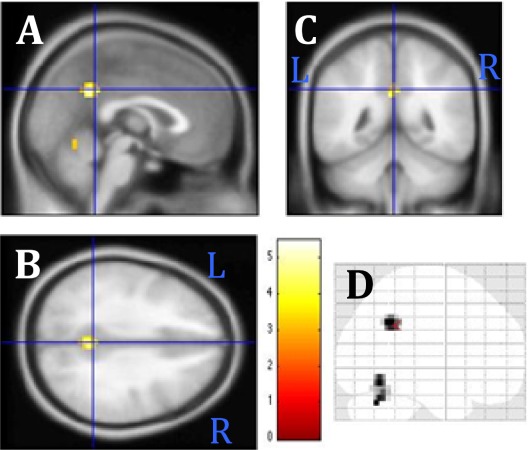

Activity of the precuneus to Bad Feelings was higher before psycho-spiritual healing (Baldwin et al., 2016).

It is, however, difficult to interpret a 23 voxel decrease in precuneus activity in 14 subjects as a reflection of such a complex therapeutic change, especially since this brain region is involved in both self-referential processing and episodic memory retrieval.